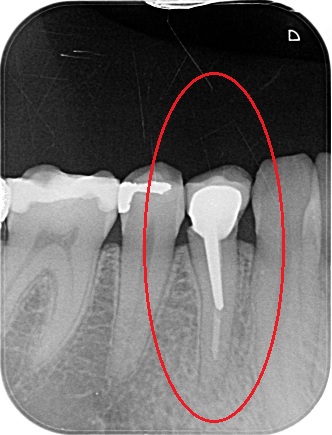

Čím přesněji jsou kanálky zaplněny (výsledek práce kontrolujeme rentgenologicky), tím lepší je vyhlídka zubu do budoucna. Známkou selhání ošetření je dlouhodobá přítomnost zánětlivého ložiska okolo zubu v kosti (lidově známé „váčky“), která záporně ovlivňuje stav organizmu a zároveň může kdykoli vést k bolesti a otoku. Naším cílem je tedy vzniku těchto ložisek předcházet.

Porovnání průměrného ošetření způsobem plně hrazeným ze zdravotního pojištění (obrázek vlevo) a ošetření způsobem nadstandardním (obrázek téhož zubu po přeléčení vpravo) mohou přinést rentgenologické snímky níže.